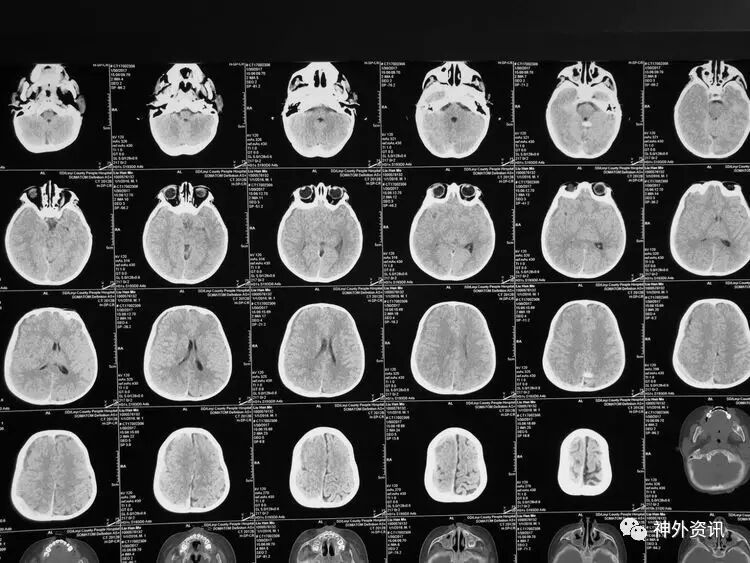

3小时后转至我院急诊科,当时查体:刺痛不睁眼,不发音,刺痛右侧肢体屈曲,右侧瞳孔5mm,对光反应消失,左侧瞳孔0.3cm,对光反应迟钝,立即术前准备并复查CT,结果示右额颞顶枕硬膜下血肿,右侧大脑半球及左侧额叶弥漫性低密度,考虑缺血,中线左移明显,脑沟及环池显示不清:

术后移动CT结果示中线移位较术前减轻,顶枕部蛛网膜下腔出血:

2017.2.1:术后2天复查颅脑CT,结果示中线居中,右侧半球低密度并SAH,左侧半球未见明显异常,左侧脑沟可见显示,双肺少量炎症,不能放松警惕,继续同前治疗。

2017.2.4:术后5天复查颅脑CT,结果示中线居中,左侧半球及环池显示清晰,右侧半球脑沟显示欠清晰,脑组织低密度较前有所好转,继续同前治疗。已加用预消化肠内营养液及促进胃肠动力药物。

2017.2.6:术后7天,复查颅脑CT示情况较前进一步好转,逐步撤掉冰毯,缓慢自然复温。

2017.2.8:术后9天,复查颅脑及胸部CT,结果显示双侧脑沟脑回及环池显示清晰。颅压控制,拔除引流管探头,头部敷料稍加压包扎,此时已更替力月西为丙泊酚,停用呼吸机。